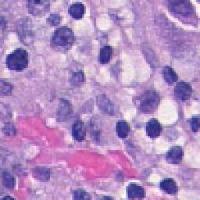

Medical Diagnostics & Research: Researchers and healthcare providers can use LDANN-BASIC to assist in the identification of lymphocyte classes, helping to diagnose diseases like leukemia or lymphoma more efficiently and enhancing our understanding of the immune system.

Pharmaceutical Development & Drug Testing: The model can be employed in pharmaceutical labs to study the effects of new drugs on lymphocyte populations, contributing to the development of more effective medications or therapies targeting specific immune conditions.

Automated Clinical Laboratory Systems: LDANN-BASIC can be integrated into automated image analysis workflows within clinical laboratories, streamlining the process of analyzing patient samples and reducing the risk of human error in lymphocyte classification.

Educational Purposes: The model can serve as a teaching tool for medical students, clinical laboratory scientists, and immunology researchers to learn and visually understand different types of lymphocytes, thereby improving their skills and knowledge in the field of histology and pathology.

Remote and Telemedicine Diagnostics: LDANN-BASIC can be used in remote healthcare settings or telemedical diagnostic systems, enabling healthcare professionals to analyze blood samples from patients even if they are located in rural or remote areas with limited access to specialized labs.